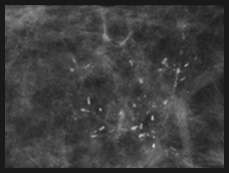

Fine Linear Calcifications

Fine linear or fine linear branching: thin, linear and usually discontinuous calcifications which represent calcified necrotic debris within a duct compromised by carcinoma. When these calcifications are new and present in a segmental distribution, they are considered a BIRADS 5 category finding.